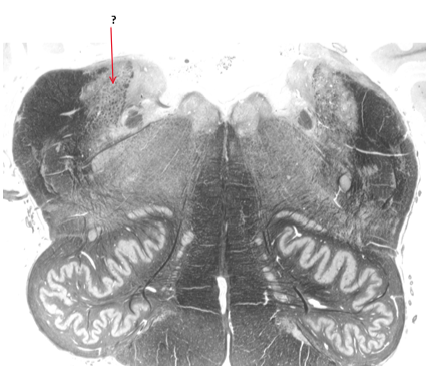

Name this, state its function, divisions and pathway.

Pyramidal tract.

Voluntary control.